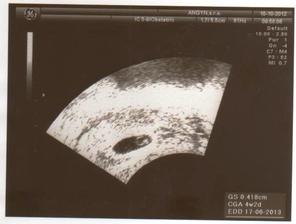

10.10.2012 - 6tt. návšteva poradne, odbery, USG, tlkot srdiečka, bábo má 4.4mm.